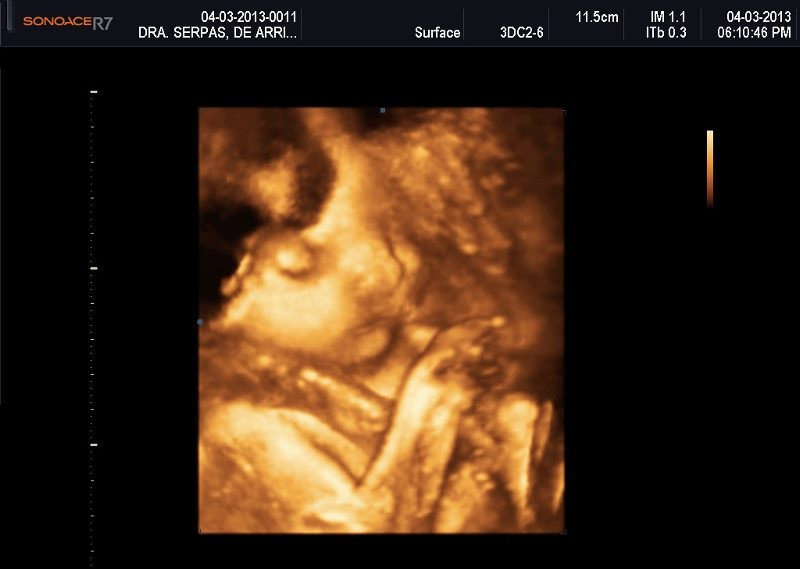

Varias ultrasonografías en 2D y 3D

Envíado por Dr. Nelson Menjívar Sarco